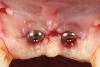

After 3 months of submerged healing, the operated area presented with limited keratinized mucosa on the buccal aspect (Figure 8). Therefore, a flap with two vertical incisions was designed starting from the palatal aspect of the two submerged implants. In addition, the mid-palatal portion of the flap was further extended toward the palatal aspect to obtain a roll flap that was de-epithelialized with a bur and eventually rolled to increase the interproximal soft tissue between the two implants (Figure 9). The flap was elevated in split-thickness fashion, with the soft tissue on top of the implants being removed to identify the cover screws (Figure 10). A substantial increase in soft-tissue thickness was observed at the buccal aspect of the implants compared to the first surgical procedure (Figure 11), when the implant fixtures were visible through a thin layer of connective tissue fibers adherent to the implant surfaces. The cover screws were removed, and temporary titanium abutments were connected.

Fig 11. Split-thickness flap elevation. Note the increased soft-tissue thickness on the buccal aspects of the implants.

Figure 11